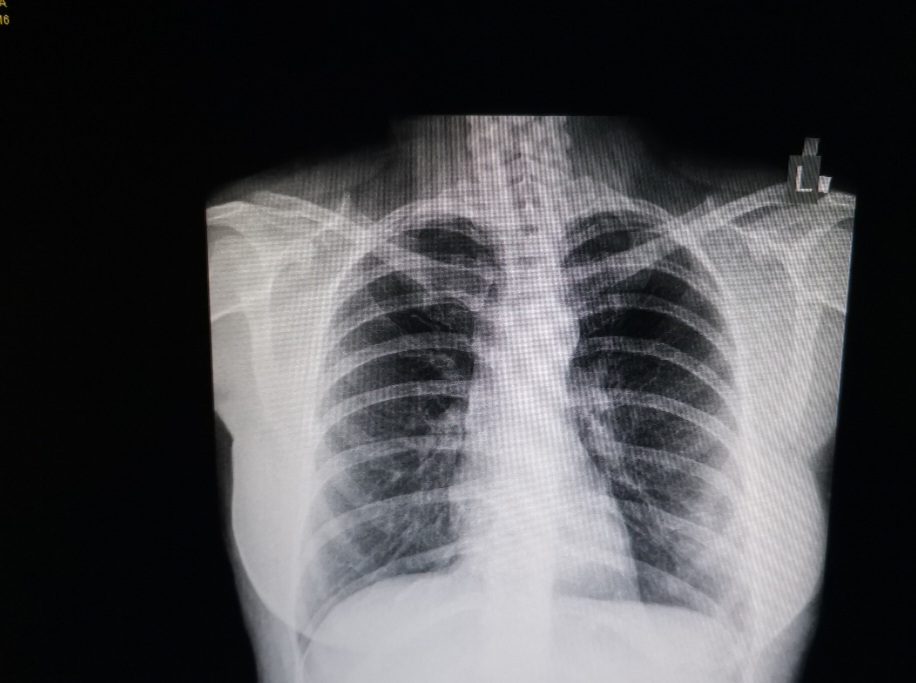

Pregled je besplatan, a obavlja se metodom niskodozne kompjuterizovane tomografije (CT). Za zakazivanje pregleda potrebni su lični podaci (ime, prezime), datum rođenja ili jmbg i kontakt telefon.